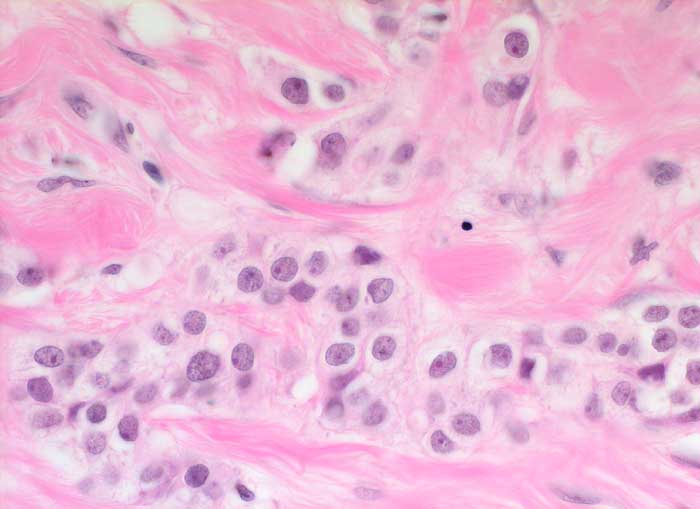

PathoPic – image database / PathoPic ID 5596 - hoch differenziertes invasiv duktales Mammakarzinom G1

hoch differenziertes invasiv duktales Mammakarzinom G1

Solide Tumorzellstränge eingebettet in reichlich Bindegewebe. Die Tumorzellen zeigen lediglich geringe Atypien und sind nur wenig grösser als normale Brustdrüsenepithelien.

4 cm Dm derber Tumor Mamma rechts oben aussen.

Histologie

400